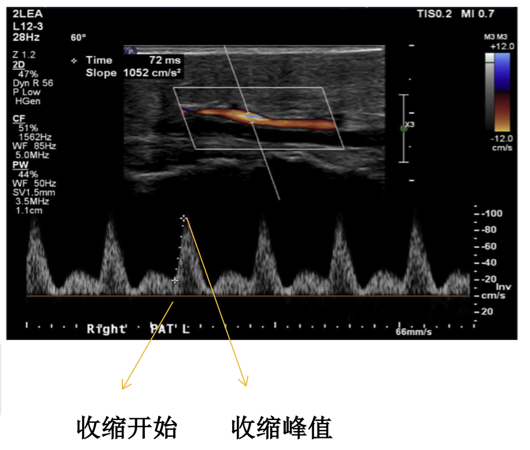

足部动脉加速时间(PAT):

主要测量足底外侧动脉的充盈速度和时间,反映微循环通畅性。具有无创、可重复、客观等优点,但依赖操作者的超声技术。

图:PAT操作示意及图像